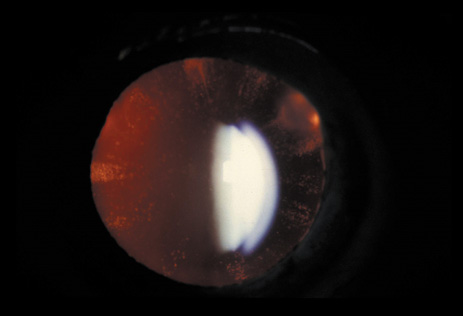

Neurofibromatosis 2 (NF2) is an autosomal-dominant (AD) disorder caused by mutations that inactivate the NF2 tumor suppressor gene. Multiple central and peripheral nervous system tumors and ocular abnormalities are common in NF2, and bilateral vestibular schwannomas (acusticus neurinoma) are pathognomonic for the disease. Constitutional nonsense or frameshift NF2 mutations are associated with severe NF2 (i.e., earlier onset of symptoms and more tumors), splice site mutations with variable disease severity, and missense mutations with mild disease. Cataracts are the most common nontumor and ocular manifestation in NF2, and are prevalent in about 60% to 80% of NF2 patients. In animal models, lens fiber cells that are more differentiated express less NF2 protein than the epithelial regions of the lens, which suggests that the NF2 protein may play a role in lens epithelial cell migration or elongation. In one study,8 the overall prevalence of cataracts in NF2 was 33%, but was significantly lower in patients with somatic mosaics and in individuals with new, as yet unknown mutations, and onset of symptoms above the age of 20 years than in patients with classic NF2, nonsense, or frameshift mutations. Of the NF2 patients with cataracts in that study, 29% were diagnosed with cataracts at an age below 10 years, and 47% were diagnosed under the age of 20 years. In 70% of the patients cataract diagnosis preceded nonocular signs or symptoms of NF2. Cataracts typically present as posterior subcapsular plaque-like opacities (Figs. 3 and 4). Other ocular manifestations include retinal hamartomas, optic nerve sheath tumors, fibrotic maculopathies, and perineural calcification of the optic nerve.9

Fig. 4. NF2. Paracentral plaque-like retrolental opacity of NF2 in retroillumination view. (Courtesy of Dr. F.D. Ellis, Zionsville, Indiana.)